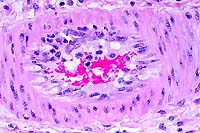

40x

- Case 24-2. Lung. Alveolar septa are thickened by hypertrophic

type II pneumocytes, and alveoli are often filled with cellular

debris and rare multinucleate giant syncytial cells bearing bright

pink intranuclear and intracytoplasmic inclusions.